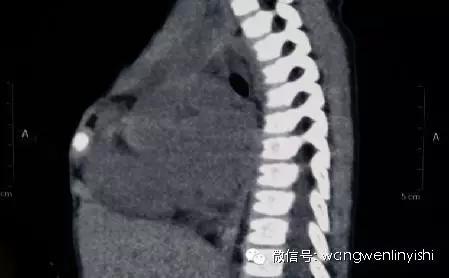

患儿3岁,自幼发现胸骨上半裂开,经检查发现先天性心脏病,室间隔缺损。术前查体发现胸骨上半完全裂开,中间明显凹陷,可以看到心脏搏动。心前区可闻及收缩期杂音。CT检查发现胸骨上半正常结构消失,两侧肋软骨与裂开的胸骨相连。心脏超声提示室间隔缺损。

(裂开的中部深面为主动脉弓)

(侧外片显示,前胸壁结构明显破坏)